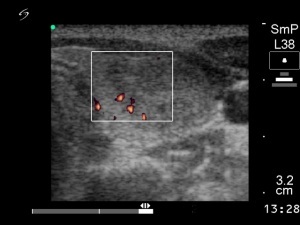

First session of sclerotherapy (1st row of images)

Clinical presentation: a 27-year-old woman was referred for evaluation of a multinodular goiter. The lesion in the left lobe has increased in the past two years and caused neck discomfort.

Palpation: a not firm nodule in the left lobe.

Functional state: euthyroidism with TSH 0.93 mIU/L, FT4 14,3 pM/L.

Ultrasonography: the thyroids were echonormal. There was a small lesion with a maximal diameter of 7 mm in the right lobe and a larger nodule in the left lobe. Both were echonormal.

Aspiration cytology resulted in benign colloid goiter.

We suggested surgery because of the compression signs. The patient told us that she is a cook in a seafarer and she has the opportunity to miss from the work only for a couple of weeks in the subsequent years. We advised ethanol sclerotherapy. Six sessions of ethanol was given. A total amount of 13.7 mL ethanol was administered in six session in 5 weeks.